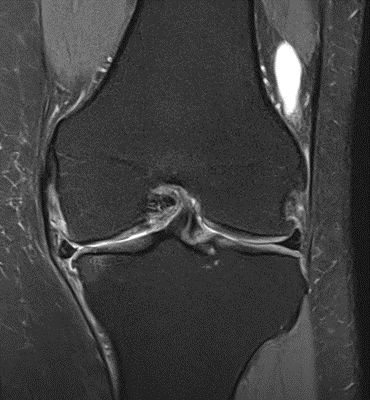

MRIs of Group 1

To provide a comparative perspective, additional MRI scans from Group 1 are shown subsequently. While patients in this group also displayed reductions in bone marrow edema, effusion, and synovitis, the improvements appeared less pronounced than those seen with the combined therapy. Pre-treatment MRI scans revealed extensive edema and synovial inflammation, which were partially reduced at the 2-month follow-up. However, residual joint effusion and subtle signs of inflammation remained present in some cases. These findings further support the potential benefit of combining the ChondroFiller® liquid with MSC therapy to achieve more comprehensive structural improvements and facilitate enhanced cartilage regeneration (Figures 30-41).

Figure 30: Female, 72 years, pre-intervention MRI.

Figure 31: Female of figure 30, two-month follow-up MRI: MSC only.